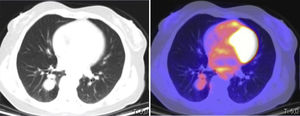

This was a 53-year-old woman, never-smoker with a history of invasive ductal carcinoma of the breast, operated 10 years previously with quadrantectomy and treated with chemotherapy and radiation therapy. The patient was initially examined for a respiratory infection with productive cough associated with wheezing, dyspnea on exertion, and oppressive chest pain. Chest computed tomography (CT) revealed a polylobulated pulmonary nodule in the right parahilar lower lobe measuring 2.1cm, that showed weak to moderate metabolic activity on positron emission tomography (PET-CT) (SUVmax: 2.68) (Fig. 1). Clinical laboratory results and lung function tests were normal. Bronchoscopy showed a pinkish exophytic vascularized mass of soft consistency with necrotic areas that occluded practically the entire basal lobe bronchus, and appeared to originate from an accessory bronchus in the posterior wall.